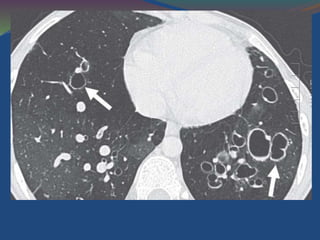

Cystic bronchiectasis

Cystic bronchiectasis is characterized by thin-walled cystic

spaces that connect with proximal airways, with or without

spaces with fluid levels

Cystic bronchiectasis Cystic bronchiectasisis characterized by thin-walled cystic spaces that connect with proximal airways, with or without

• 52.

Cystic bronchiectasis ischaracterized by thin-walled cystic spaces with fluid levels